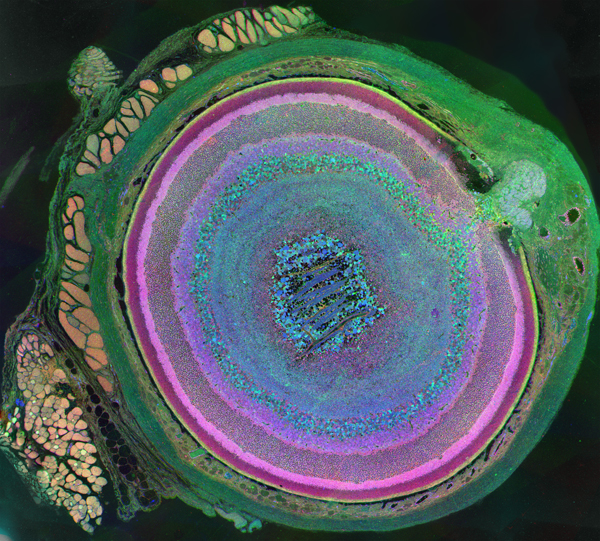

This image of the gymnast Annabeth Eberle taken by Ann Torrence, was captured with a lens that obviously can get the job done. Unfortunately, this lens and its equivalent from the Canon line are fabulously expensive. So expensive in fact, that they rival or exceed the cost of my camera body. What most SLR photographers do come to realize however is that the camera bodies typically end up being only a small percentage of the overall costs of a photographic kit. Lenses are the objects that occupy most of the total financial outlay and why within your platform of preference (Canon vs. Nikon), the lenses have historically been compatible over many models and model years showing the importance of backwards and forwards compatibility along with carefully considered design and engineering that go into every new lens from these companies. After all many of their customers invest a not insignificant amount of money in their glass and would like to know it will not be obsolete within the near future, which brings up the topic of maintaining the photography habit. Ann suggested to me that I take some of the images I create for our research and submit them to SIGGRAPH which would in fact, be perfect for submission given their computational origins. I have already optimized the three images shown here and had them made into prints for display as art. They do end up as being rather stunning in our house and of our friends. If any of you are interested in a print of one of these images, let me know and we can discuss what is involved in creating them and how to obtain one. There are also a few others as well…..